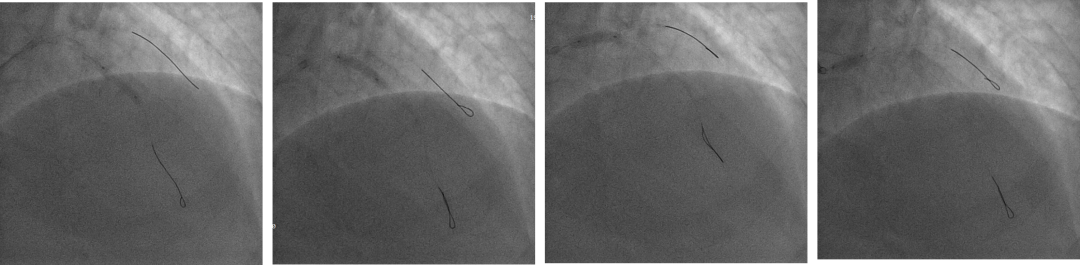

7F XB3.5,Cosair,Runthrough中间支保护,Pilot200正向进入D1,Pilot200 无法通过病变,交换Judo导丝

更换Judo3顺利到达LAD远端,Cosair跟进交换Runthrough

双侧造影,RCA 7F AL1.0,Runthrough导丝置于远端。

LCA 7F XB3.5,Cosair135,尝试Pilot200失败,进入假腔,Judo3成功通过闭塞段,换入Pilot150后,仍然进入假腔,再次使用Judo导丝,进入前降支远端,微导管造影,证实为真腔内,送入工作导丝。

Tip injection确认真腔,更换runthrough,2.0*20mm球囊预扩。